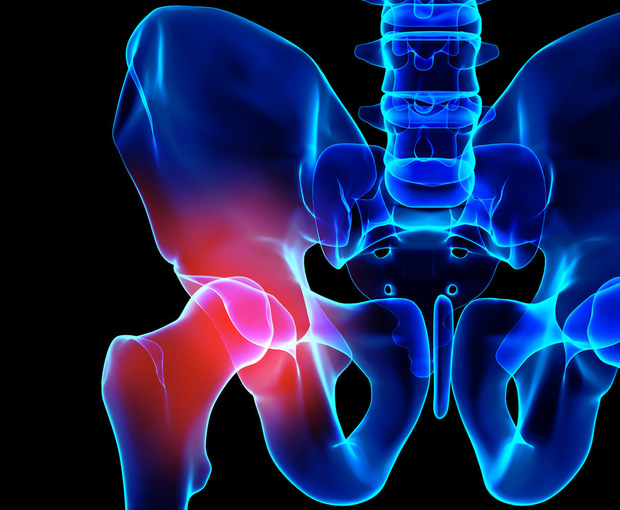

Have you ever had a nagging pain in the region of the pelvis or hip? Pain or discomfort in the pelvic region and the hip may be related. Since the hip is a weight bearing joint, pain and discomfort in the hip can cause problems with sitting, standing and walking.

The bones of the hip and pelvic region act as protection for internal organs such as the bladder. Depending on the severity of the injury, a hip fracture can result in internal bleeding, difficulty urinating and abdominal pain.

Fractures in the pelvis and hip typically result from high-impact trauma. Participation in athletic programs, bicycling injuries and vehicle accidents can also cause fractures.

No one wants to experience pain and discomfort, especially the kind that prevents you from doing simple things like sitting, standing and walking. From a human anatomy standpoint, pain in the hip and pelvis affects your ability to bear weight on those joints. In fact, problems in the lower back are related to hip pain and vice versa.